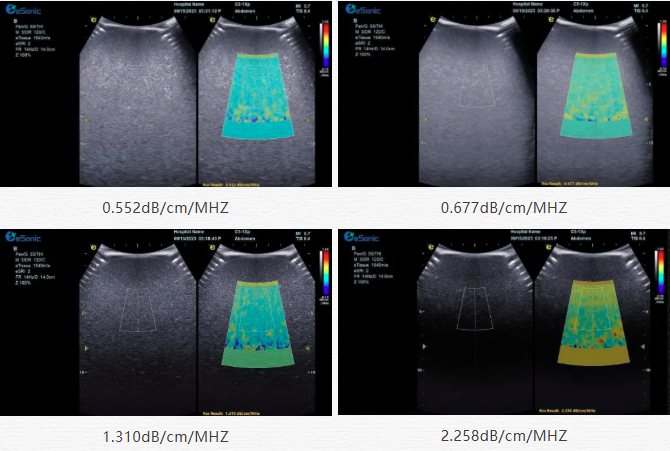

该技术基于声波在介质传播时的衰减,衰减由声吸收、反射、散射及波束扩散所致,声衰减系数(α,单位 dB/cm?MHz,与超声频率和传播距离成正比)可通过测定同频超声波在组织中的衰减程度,借回波信号分析预测声衰减系数或衰减率来评估组织特性。

目前市面常用瞬时弹性成像或仿体参照法,存在适用性、准确性差及无衰减图局限。3377体育则采用准确度更高的 ALA 幅度损失衰减法,超声波深度传播时回波幅度渐降,其对数与深度有良好线性关系,声衰减量与传播衰减系数成函数关系,调节取样框大小位置可实时得样框内组织衰减系数,用于定量评估病变程度。

声衰减定量成像技术的应用范围非常广泛,包括肝脏疾病、乳腺肿瘤鉴别、肾脏病变以及肌肉骨骼系统等多方面的病变。712a8084746869e803a3684e2526ee4.png肝脏疾病诊断在脂肪肝的评估中,脂肪作为一种声衰减介质,超声波在脂肪肝内的传播会产生衰减,肝脏中脂肪组织比例越大,超声衰减就越高。在肝硬化患者的肝脏中,肝脏组织的纤维化和结构改变会导致超声声衰减特性的改变。声衰减成像技术可以帮助医生观察肝脏实质的变化,辅助判断肝硬化的程度,同时对于监测肝硬化治疗过程中的病情变化也有一定的价值。